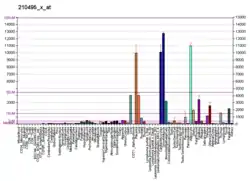

- ↑ Chicco D, Alameer A, Rahmati S, Jurman G (November 3, 2022). "Towards a potential pan-cancer prognostic signature for gene expression based on probesets and ensemble machine learning". BioData Mining. 15 (1): 28. doi:10.1186/s13040-022-00312-y. eISSN 1756-0381. PMC 9632055. PMID 36329531.